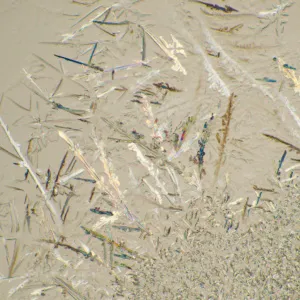

MAGUS Bio 230T – биологический тринокулярный микроскоп для лабораторных и исследовательских наблюдений в медицине, фармацевтике, криминалистике, биотехнологии и других областях науки. Применяется для работы с плоскими полупрозрачными и прозрачными образцами биологического происхождения: тонкими срезами и мазками. Оснащен ахроматической оптикой и галогенной подсветкой, наблюдения ведутся в проходящем свете в светлом поле. Микроскоп рассчитан на установку дополнительных аксессуаров для использования большего количества методов наблюдений: темного поля, фазового контраста, поляризованного света.

Чтобы расширить возможности микроскопа MAGUS Bio 230T, достаточно дооснастить его аксессуарами. Доступны окуляры и объективы, цифровые камеры и калибровочные слайды, конденсоры темного поля, устройства для наблюдений в поляризованном свете и с использованием фазово-контрастной микроскопии.

- Устройство простой поляризации